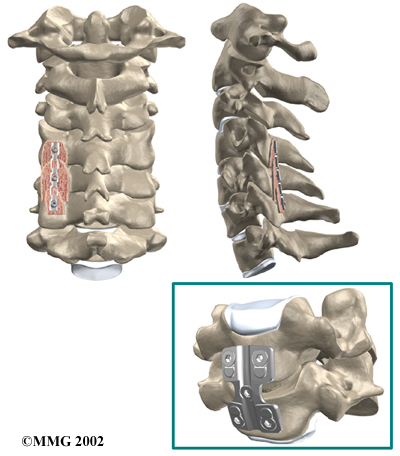

Cervical Fusion

A fusion surgery joins two or more bones into one solid bone. The purpose for doing spinal fusion is to increase the space between the vertebrae and to keep the sore joint from moving. This is usually done by placing a small block of bone graft in the space where a disc was removed. Opening up more space enlarges the neural foramen, takes pressure off the nerve roots, and eases tension on the facet joints. Cervical fusion is used to treat neck problems such as cervical radiculopathy, disc herniations, fractures, and spinal instability. There are two main types of fusion for neck problems.

- Anterior Discectomy and Fusion: Anterior discectomy and fusion is done through the front of the neck. After taking out the disc (discectomy), the disc space is filled with a small graft of bone. The bone is allowed to heal, fusing the two vertebrae into one solid bone.

Small Graft of Bone

-

- Posterior Fusion: In posterior fusion, the surgeon lays small grafts of bone over the back of the spine. When these bones heal together, they fuse the two vertebrae into one solid bone. Posterior fusions in the cervical spine are primarily used to treat fractures of the neck.

Posterior Fusions

The bone graft needs time to heal in order for the fusion to succeed. This requires the neck to be held still. After cervical fusion surgery, patients usually have to wear a special neck brace for several months. These neck braces are often bulky and restrictive. Recently, surgeons have begun using metal plates and screws (often referred to as instrumentation) to lock the bones in place. The instrumentation is fastened to the vertebrae, where it holds the bones still while the graft heals.

Locking the Bones in Place